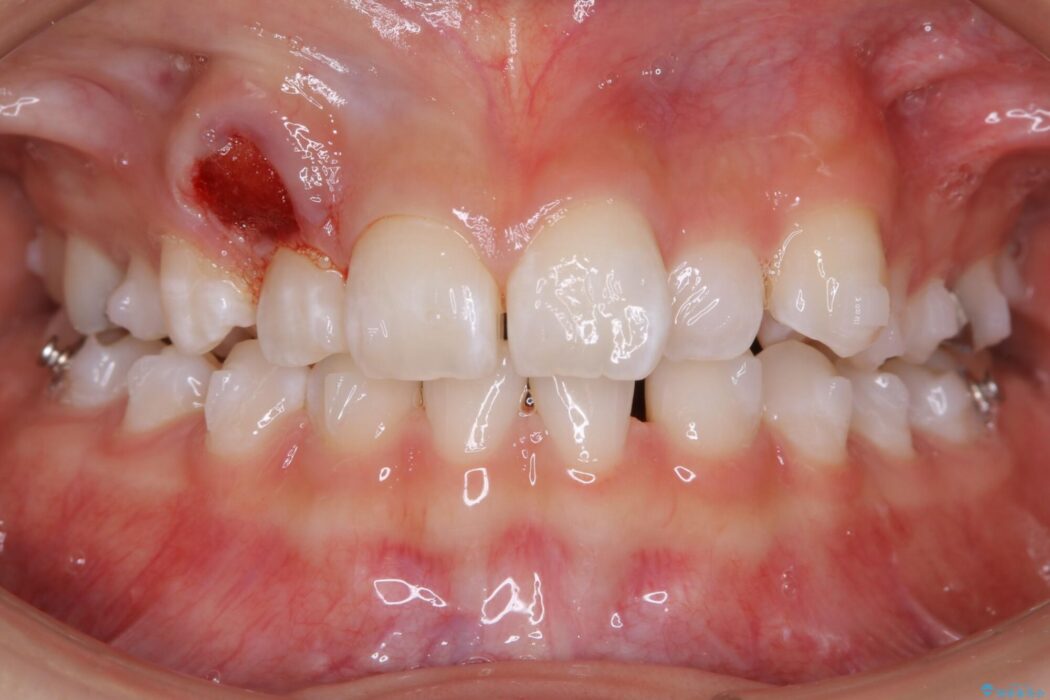

飛び出た八重歯による歯列のガタガタを主訴に来院されました。

診査したところ叢生だけでなく生まれつき永久歯の欠損、いわゆる先天欠如により歯の本数が少ないため噛み合わせなどにも影響が出ている状態でした。

特殊な状況からの矯正治療となるため、抜歯する本数や位置、歯列を整えるにあたって必要なスペースの確保を慎重に計画し、インビザライン コンプリヘンシブパッケージでのマウスピース矯正を行いました。